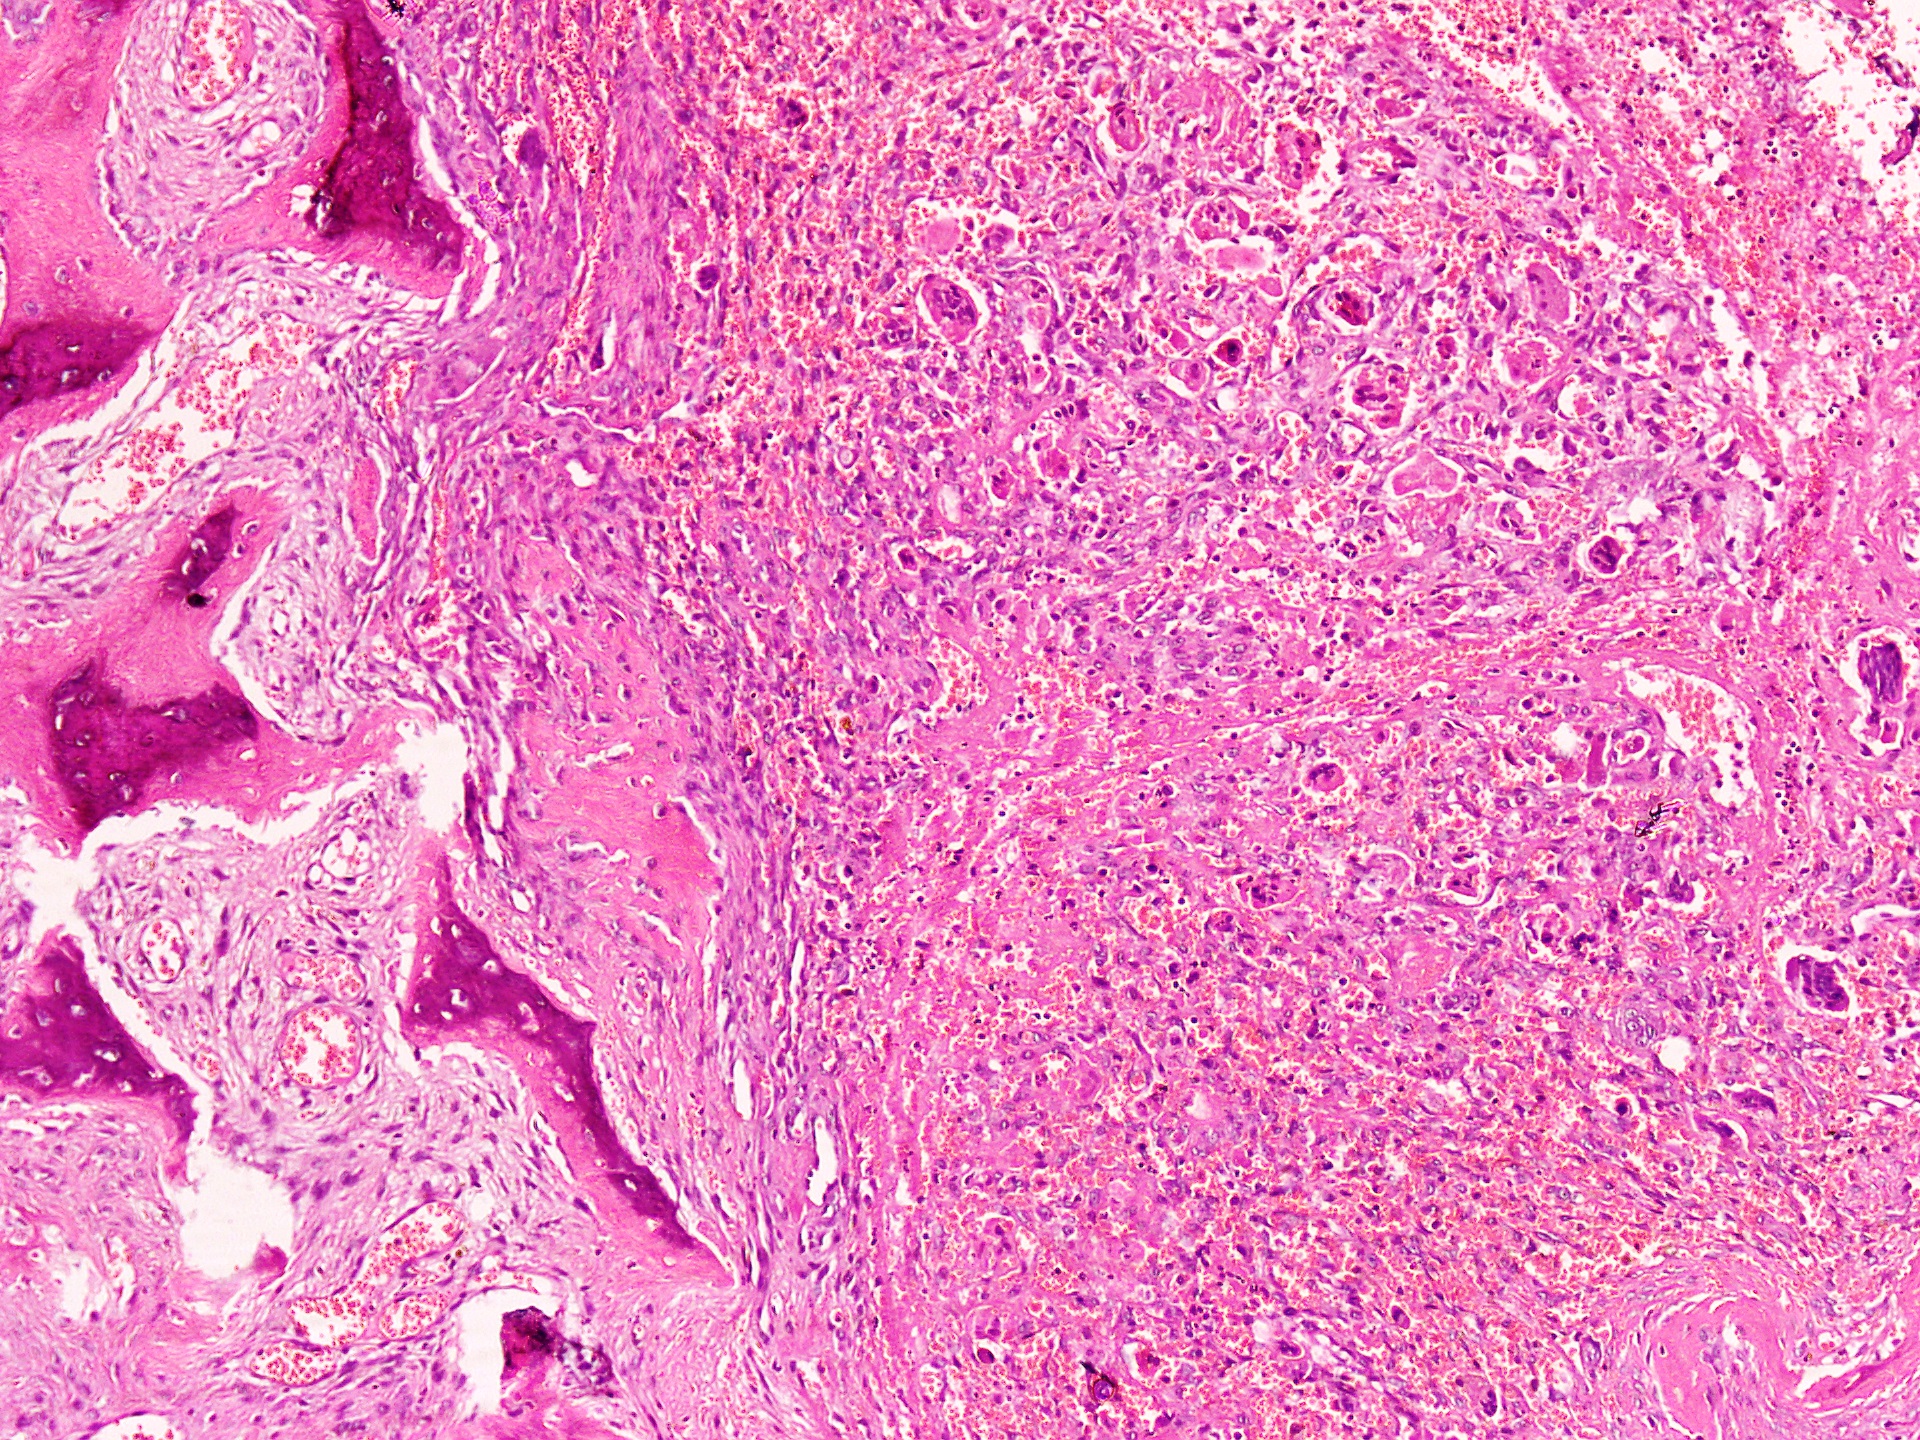

Microscopic (histologic) description

- Lobular pattern composed of groups and clusters of osteoclast-like multinucleated giant cells

- Vascular fibroblastic stroma

- Hemorrhage and hemosiderin deposits

- Tunneling resorption of adjacent uninvolved bone (J Int Oral Health 2015;7:50)

Microscopic (histologic) images

A 50 year old woman presented with a swelling on the right side of her face that gradually increased in size over last 3 years. It was associated with pain, trismus and inability to open her right eye. She also had history of frequent headaches, abdominal pain and renal stones. Xray revealed a lytic lesion within the right mandible. Incisional biopsy was performed and microscopic examination revealed a lesion (shown above). The most likely diagnosis is

B. Brown tumor of hyperparathyroidism. The photomicrograph shows a lesion composed of bony trabeculae showing resorption along with scattered osteoclast-like giant cells in a vascularized spindled stroma. These microscopic findings with above mentioned clinical and radiological features are characteristic of brown tumor of hyperparathyroidism. Aneurysmal bone cyst affects young adults and shows large blood filled spaces with intervening septae containing fibroblasts and giant cells. Central giant cell granuloma produces radiolucent lesions in children and young women and shows osteoclast-like giant cells near hemorrhagic areas, cellular vascular and fibrous stroma and new bone formation at edge of lesion. Cherubism shows bilateral involvement of mandible and maxilla in young individuals and histology is similar to central giant cell granuloma. Giant cell tumor rarely affects mandible and shows uniform distribution of osteoclast type giant cells among mononuclear cells.